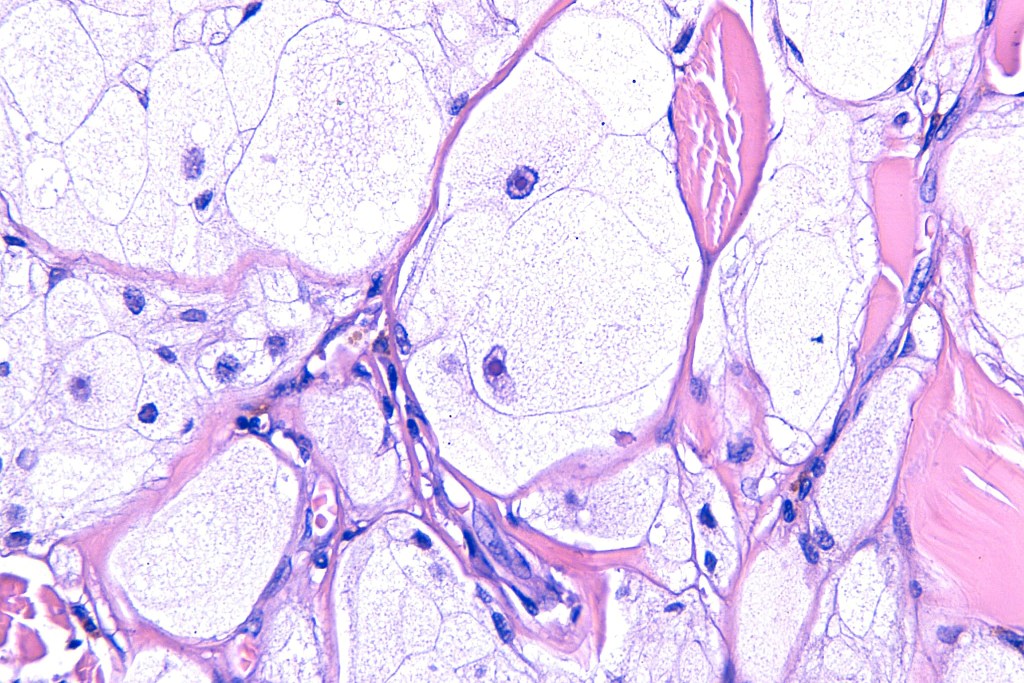

•Enlarged cells with copious eosinophilic, foamy or clear cytoplasm (some authors include melanoma with clear cell change in the same category)

•Variable pigmentation

•Nuclei vesicular or hyperchromatic

•Pleomorphism is not generally marked and indeed can be very subtle

•DPAS granules

•Thought to be a result of abnormal or degenerative melanosome change